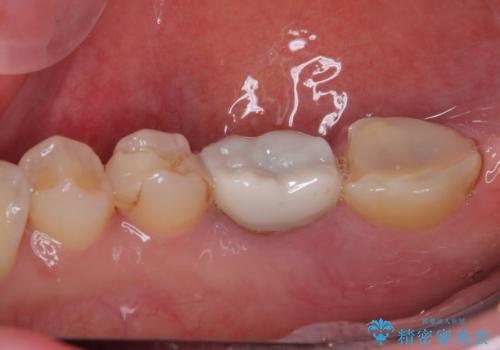

破折して抜歯が必要となった奥歯 オールセラミックブリッジ治療

- 奥歯から膿が出てくることを気にして来院された患者様です。

診察より、奥から2番目の歯が割れている可能性が非常に高いため、まずは奥から2番目の歯の状態を診断することとしました。

クラウンを外したところ、目視でも確認できる破折線が認められたため、抜歯することとしました。

抜歯後も膿の出口が消えず、一番奥の歯を診察したところ神経組織の反応がなかったため、根管治療を行うこととしました。

再度の歯を根管治療したため、抜歯した部位の補綴治療は、強度の問題からブリッジよりもインプラントをおすすめしましたが、患者様希望によりブリッジを選択しました。

一番奥の歯は歯肉から露出している高さが少なく、クラウンを装着する不十分であったため、歯冠長延長術を行うこととしました。